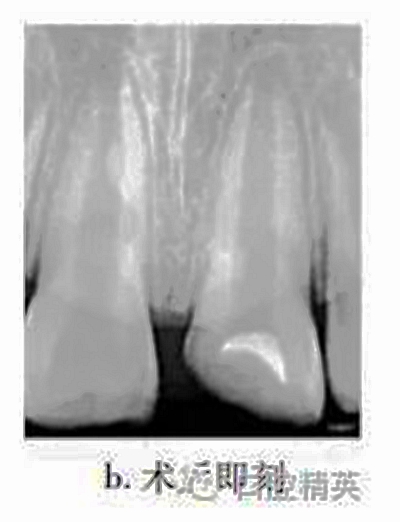

治療:局麻下調(diào)牙合,21揭髓頂,去除可能污染的冠部牙髓,達(dá)根管口處,呈整齊斷面,生理鹽水反復(fù)沖洗以去盡組織碎屑,并用蘸有少許生理鹽水的小棉球置于牙髓斷面壓迫止血,將MTA按操作說(shuō)明要求和生理鹽水按3∶1比例調(diào)和均勻呈糊狀,直接覆蓋在牙髓斷面約1mm,玻璃離子水門汀暫封(圖b)。